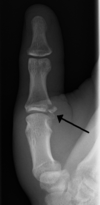

BENNETT

- Oblique fracture through base of the first metacarpal, with dislocation of the radial portion @ articular surface

- produced by direct force applied to end of metacarpal; dorsal capsular structures disrupted by dislocation; marked tenderness along medial base of thumb

• thumb spica x 4 weeks